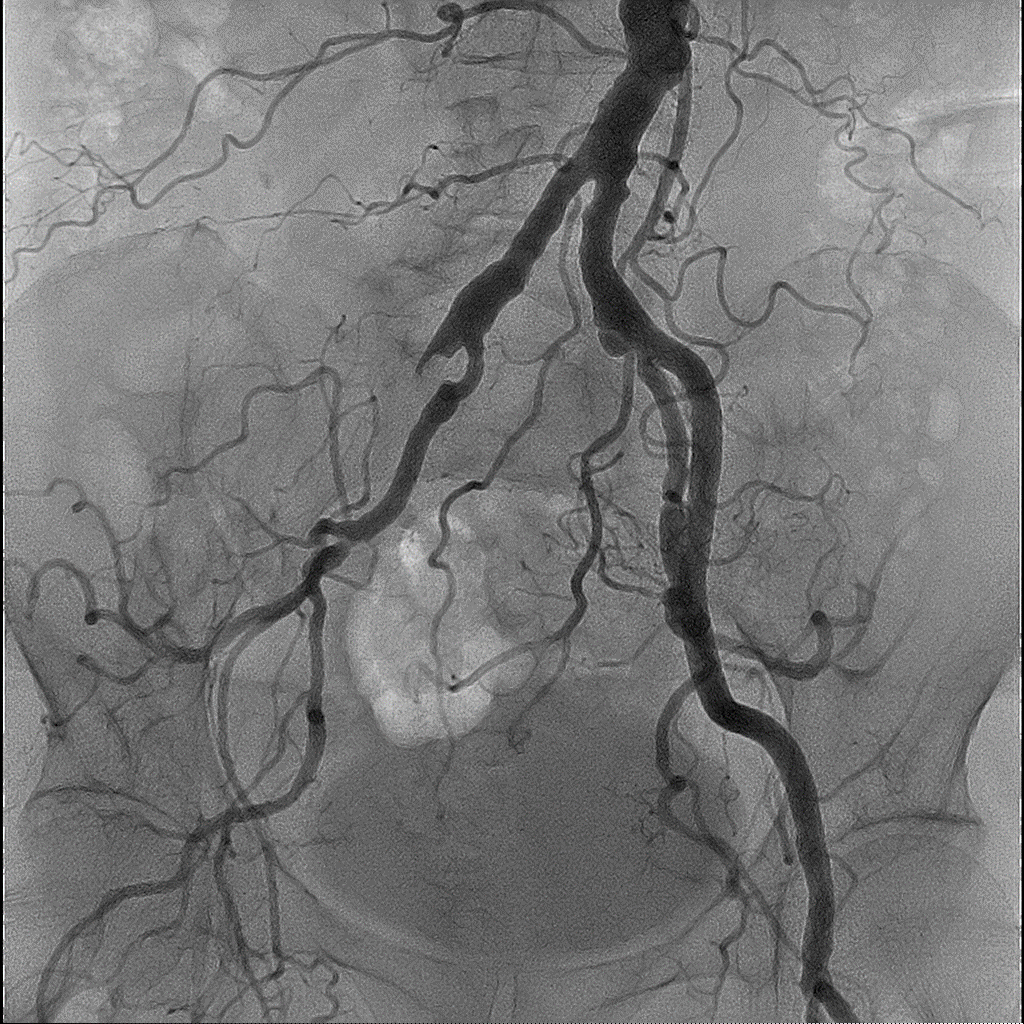

Програмне забезпечення 3D реконструкції

В основу покладена робота в режимі 3D DA або 3D DSA. Зйомку можна виконувати як з операційної, так і з пультової кімнати для зменшення дози на персонал, зі швидкістю обертання С-арки до 50°/с.

Численні режими візуалізації та реконструкції: